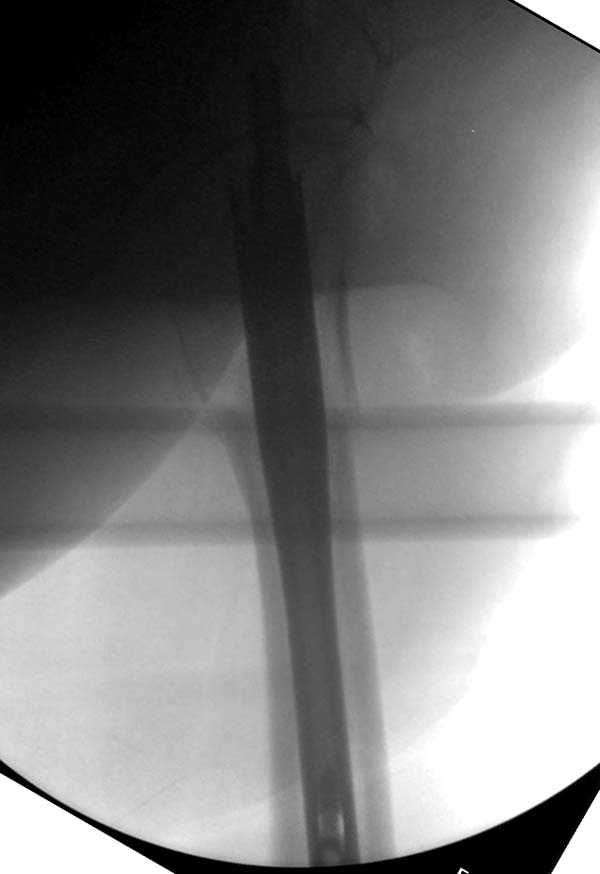

Считаем, что техническая ошибка произошла во время установки гвоздя, когда рассверливанию канала не уделили должного внимания. Канал остался узковат, и гвоздь был забит с силой. Полная нагрузка конечности приостановлена на две недели, и боли в конечности изчезли. Больная начала нагрузку и перелом срастается.-- Djoldas Kuldjanov, M.D.Associate ProfessorDepartment of Orthopedic SurgerySt. Louis University

Мне думается, что варусное положение проксимального отломка на последующих снимках не более чем проекционный феномен. Раскол же диафиза вдоль, наверняка, связан с чрезмерно насильственным введением штифта. Вообще, при реверсивных, да и обычных вертельных переломах, многие давно отказались от короткой Гаммы в пользу long-версии. Но в любом случае надо быть на 100 уверенным в подготовке канала.